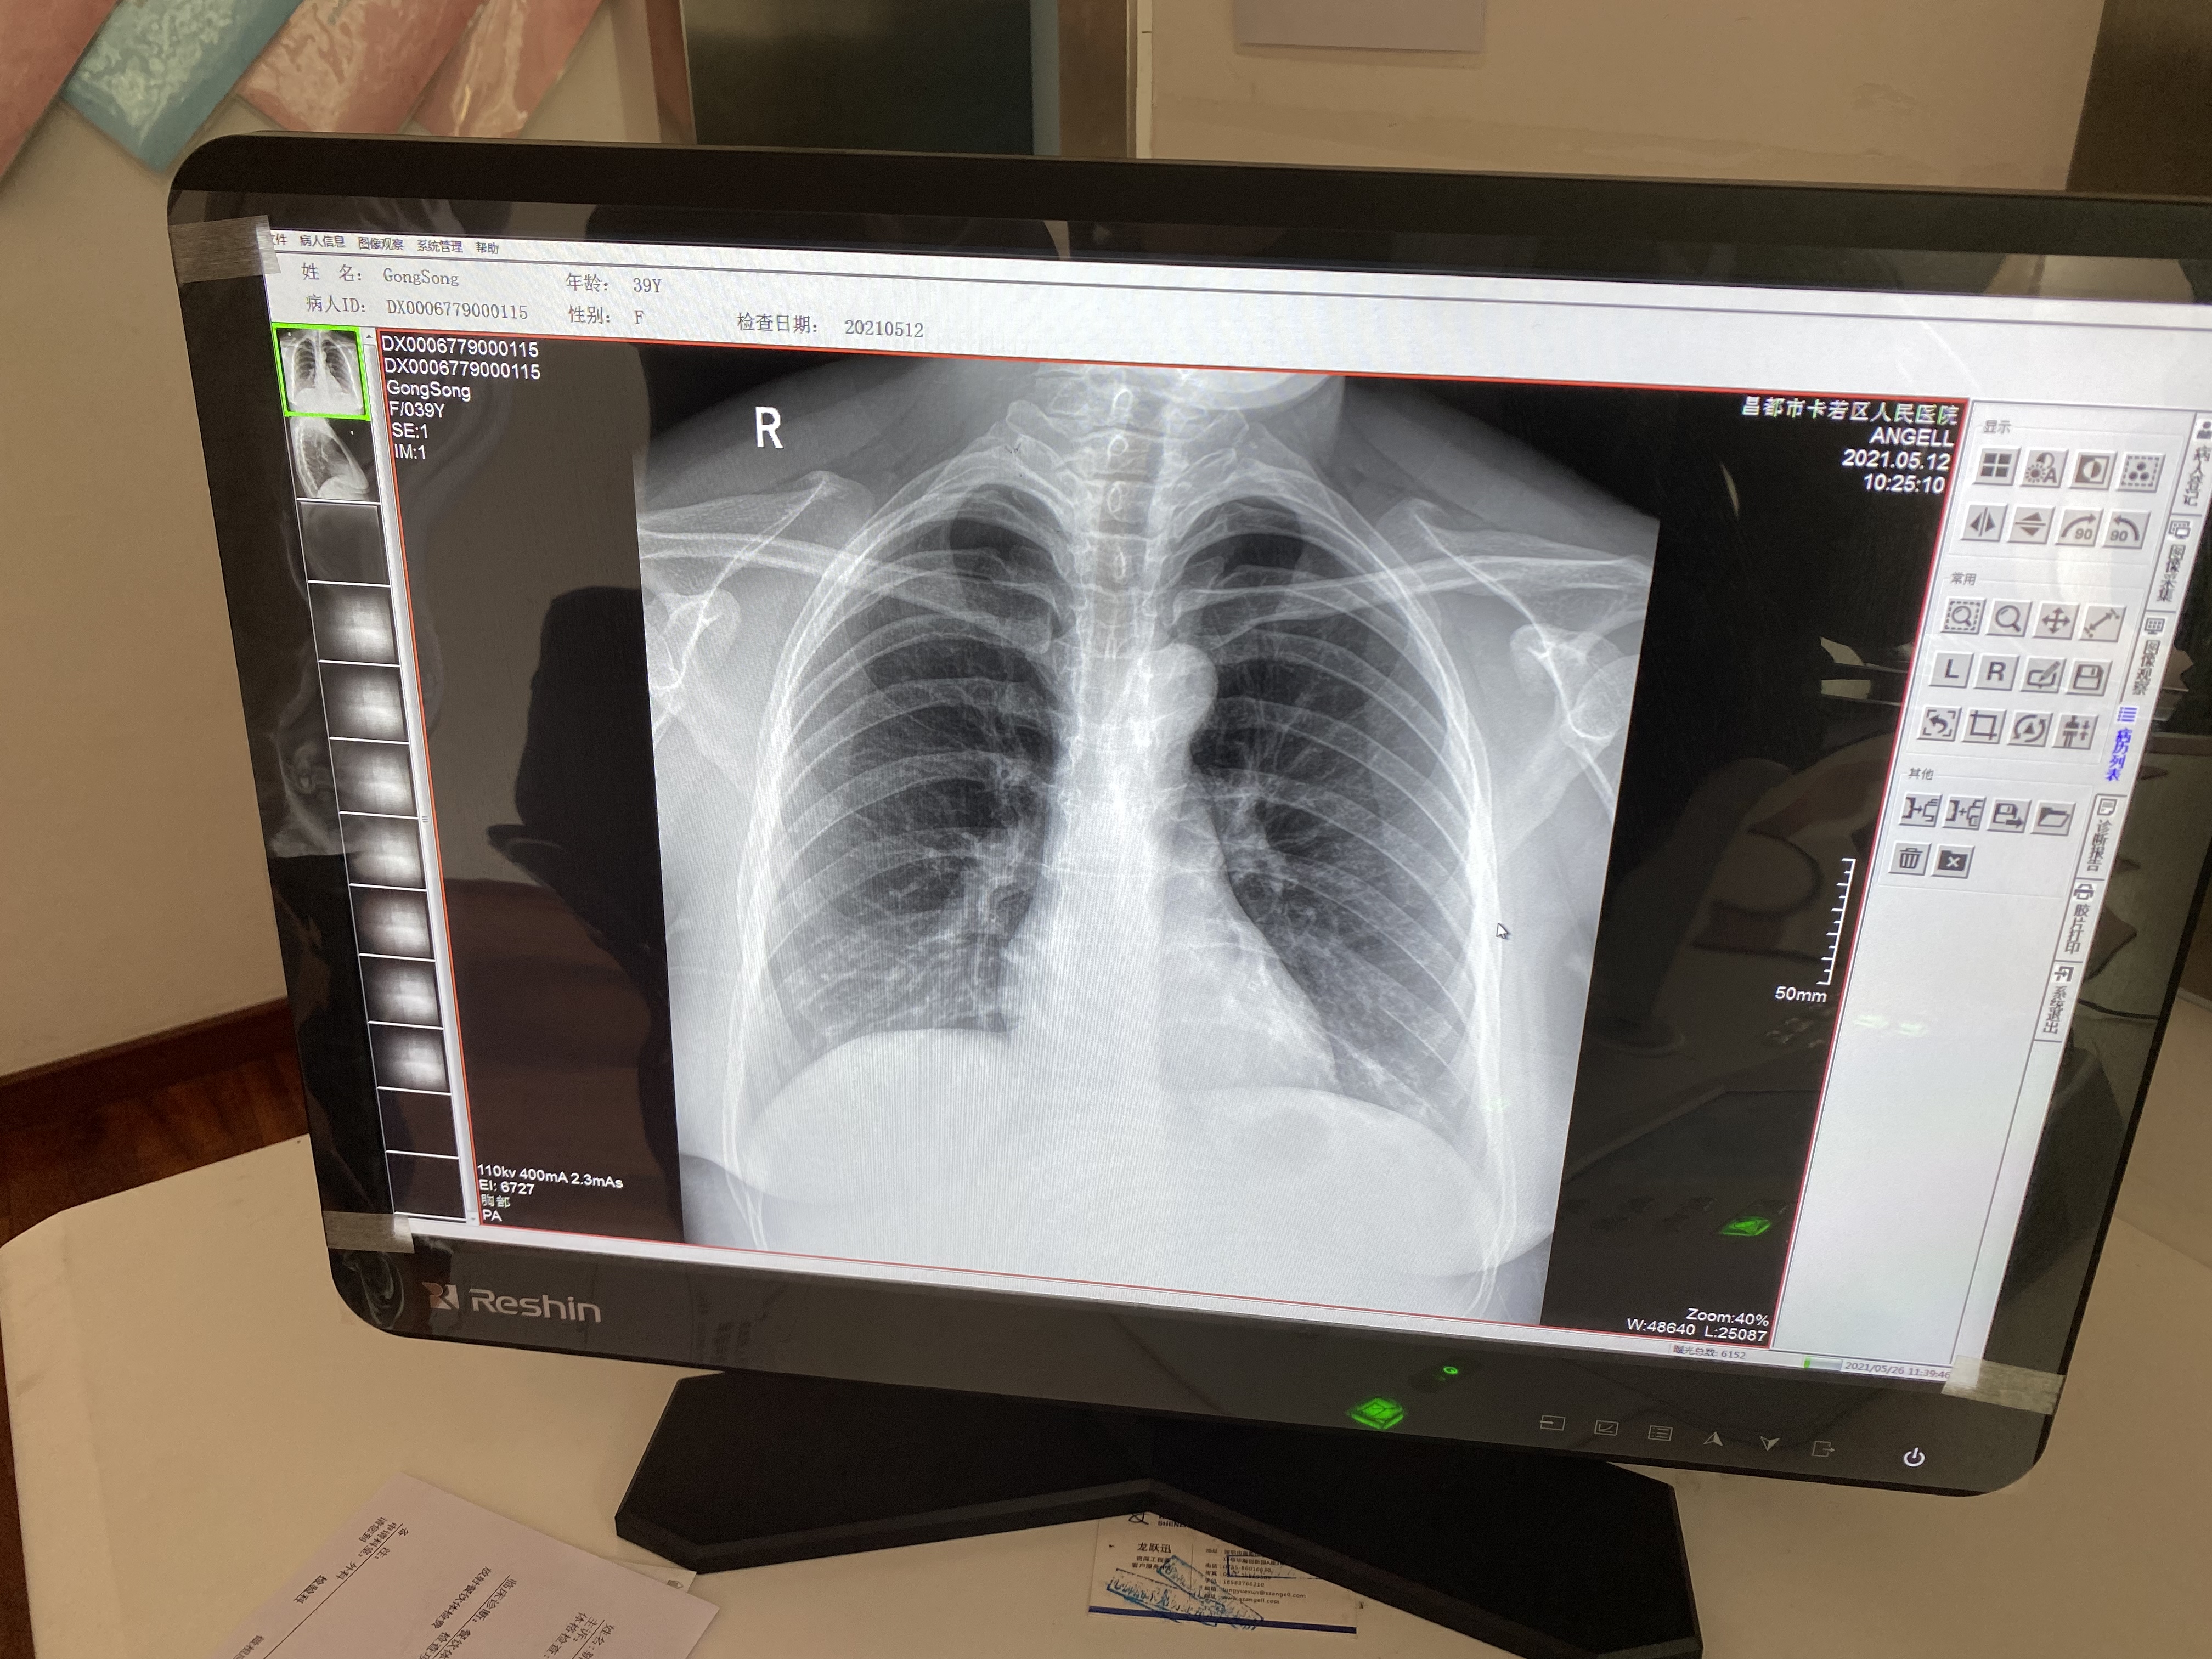

6:騰靈的胸片攝片臨床影像

作為一款動態多功能診斷專用DR設備,騰靈支持高清攝片、透視攝影、造影攝影、全脊柱攝影、全下肢攝影檢查于一身,滿足低人口密度地區的多種數字化X線攝影檢查需求。在卡若區人民醫院,每天大約有60人左右的檢查人次,來自于一區十縣 24個鎮118鄉的藏區百姓,騰靈在過去近一年的服役中贏得了放射科主任及主管技師的一致認可。

“這個設備好得很,現在我們這個醫院就1臺這個設備,每天都在給病人做檢查。摁一下摁扭它就可以立起來,體檢病人的時候我們就立起來檢查,拍出來的圖像很清楚。它也可以橫著放,拍腰椎的病人、骨關節的病人,我們摁一下就可以平放攝片。我們現在已經檢查了差不多有1多萬個病人了,機器沒有出現什么問題,工程師也會經常詢問設備的情況,這個設備美得很。”操作設備的主管技師說。